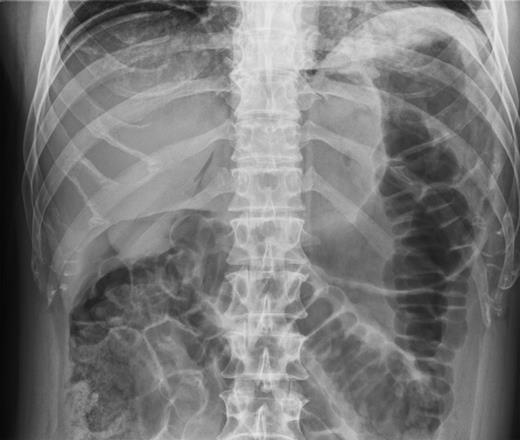

Over a year later, the same gentlemen presented to the surgical admissions unit once again with a history of acute abdominal pain. The duration and nature of symptoms were very similar to his previous admission. He again underwent plain film abdomen and erect chest radiographs that showed a large volume of free air under the diaphragm (Figs. 4 and 5).